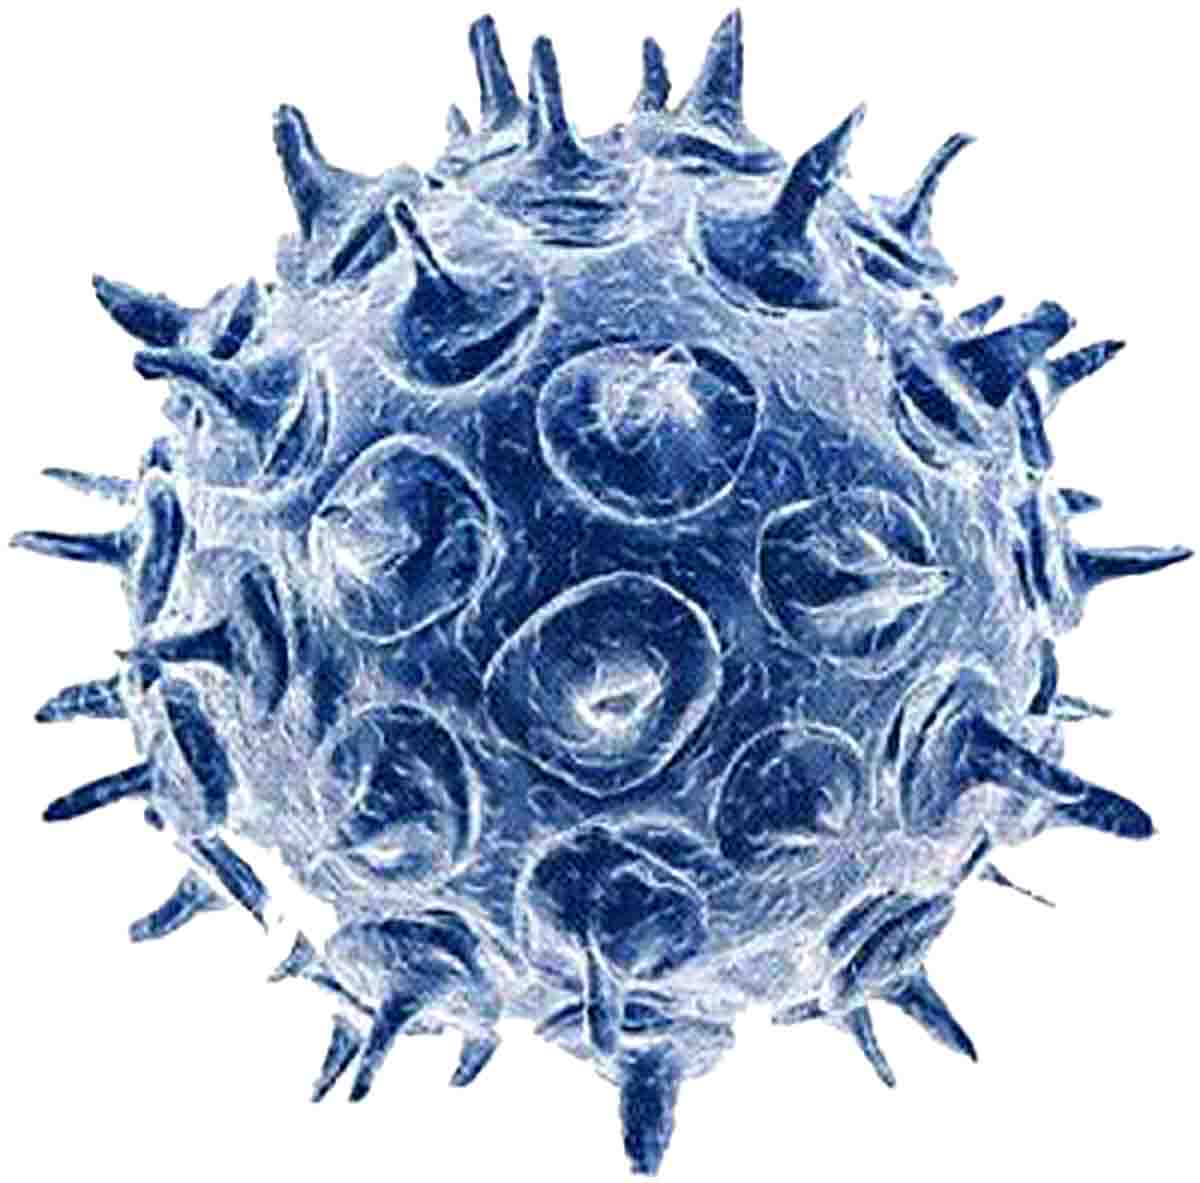

Медицинские снимки и изображения опоясывающего герпес вируса